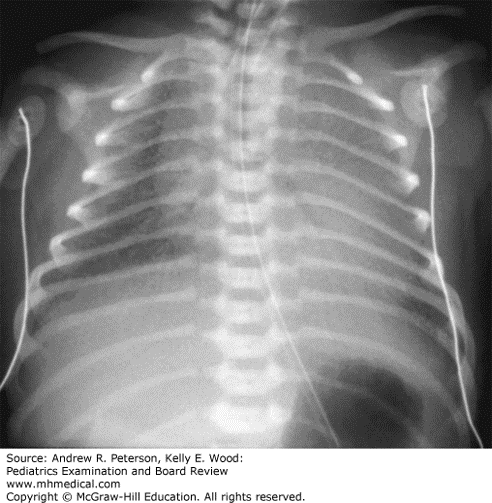

A 35-week gestational age infant is born by cesarean delivery to a mother with placenta previa. The infant girl is vigorous after delivery, with Apgar scores of 8 and 8. She is brought to her mother’s chest. Fifteen minutes later the NICU team is called because the infant is experiencing worsening respiratory distress with tachypnea, retractions, and mild grunting respirations. She is placed on nasal CPAP and admitted to the NICU. The infant continues to be tachypneic, at 80 breaths per minute, has mild retractions, and requires 40% FiO2 on CPAP. Her chest radiograph shows approximately 7-rib expansion with ground glass opacities throughout all lung fields.

Explanation: The correct answer is “B.” This infant has persistent distress on CPAP with rising oxygen and evidence of respiratory distress syndrome on chest radiograph with decreased lung expansion and findings consistent with surfactant deficiency. Although respiratory distress syndrome is most common in very preterm infants, many late preterm infants of less than 37 weeks’ gestation have surfactant deficiency, especially those who have not had spontaneous labor. If clinical symptoms continue to worsen, oxygen needs increase, or gas exchange is poor as evidenced by respiratory acidosis on blood gas measurements, then this infant should be intubated and surfactant administered through the endotracheal tube.